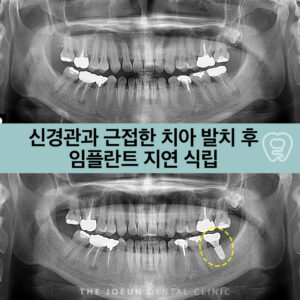

달서구치과 치아 교정 전 신경관과 근접한 사랑니 발치

달서구치과 치아 교정 전 신경관과 근접한 사랑니 발치   사랑니는 일반적으로 우측과 좌측 위아래 제일 뒤쪽으로 총 4개의 치아로 존재합니다. 사랑니가 선천적으로 모두 없거나, 1~3개 일부 존재하는 경우가 종종 관찰되기도 하는데 무조건 발치해야 하는 것으로 인식하는 경우를 볼 수 있어 현재 큰 문제를 일으키거나 혹은 향후 문제를 일으킬 가능성이 높은 더보기…